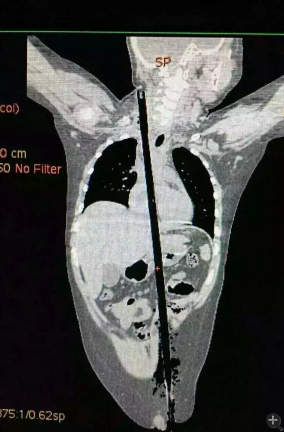

據(jù)相關(guān)知情人介紹,受傷男童24日晚在家中與小朋友一塊兒在墻頭上玩耍時,一不小心從高墻上跌落到了鄰家花圃中,讓人觸目驚心的是,該男童正好跌到了花圃中的一支長約63厘米,直徑約1.5厘米的竹棍上,竹棍自孩子的左側(cè)大腿根部直接插入腹腔并入胸腔直至右側(cè)頸部。

市兒童醫(yī)院組織專家團隊對孩子的病情進行檢查、評估后發(fā)現(xiàn),竹棍由患兒左側(cè)大腿根部插入,經(jīng)腹腔穿透胃、肝臟、膈肌入胸腔,并穿透患兒心臟,經(jīng)胸腔入頸部,此刻不能拔除竹棍,因為去除竹棍會導(dǎo)致心臟、肝臟破裂大出血導(dǎo)致休克,危及性命。

由于竹棍自心臟的右心房膈面穿入心臟,并由右房近左房頂處穿出心臟,經(jīng)右胸頂刺入右頸部,右心房破口處緊鄰右冠狀動脈,幸運的是胸腔內(nèi)大血管無損傷,在體外循環(huán)輔助下,醫(yī)護團隊異物穿出處鋸斷異物,將插入心臟內(nèi)的竹棍截斷拔除,修補心臟破損處,向上繼續(xù)尋找周圍組織的游離異物,見異物緊臨頸部大血管,經(jīng)精細手術(shù),終于抽出了異物。整個手術(shù)時間花了十多個小時。